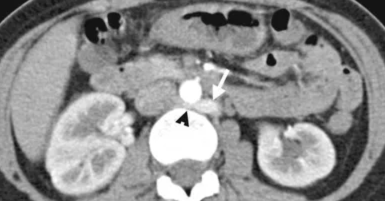

Veine rénale gauche rétro-aortique

Veine rénale gauche retro-aortique

Veine rénale gauche retro-aortique